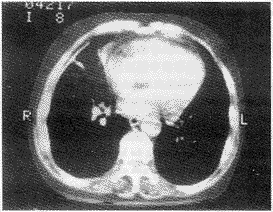

1.2.1 胸膜改变:X线片可观察到胸膜改变5例,其中1例疑为胸膜斑。CT检查发现胸膜改变高达16例,其中6例为胸膜斑,并可观察到胸膜斑钙化、小块的胸膜斑、表面不平及结节状表现(图1、2、3),还有3例脊椎旁胸膜斑(图3、4)。CT检查所见的改变在X线片上是难以发现的。

患者接触石棉23年(1955~1978年)

图2 左前侧胸膜斑及肺纤维化束